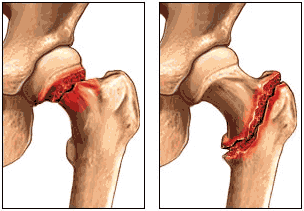

"Chúng ta đã thấy rằng cấu trúc xương xốp (mật độ xương thấp) ở hàm dưới ở tuổi trung niên là trực tiếp liên quan đến nguy cơ gãy xương sau này ở các bộ phận khác của cơ thể ", Lauren Lissner, một nhà nghiên cứu tại Viện Y học tại Sahlgrenska Học viện, nhận định.

Nghiên cứu cho thấy rằng cấu trúc xương hàm “xốp” vào khoảng 20% ở phụ nữ tuổi từ 38-54 khi kiểm tra đầu tiên được thực hiện và những phụ nữ này có nguy cơ gãy xương lớn hơn đáng kể.

Nghiên cứu cũng cho thấy rằng người càng lớn tuổi thì sự tương quan càng lớn giữa cấu trúc xương hàm xốp và gãy xương ở các bộ phận khác của cơ thể.